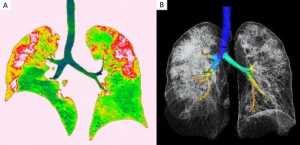

Οι σαρώσεις του, που δόθηκαν στη δημοσιότητα από την Ακτινολογική Εταιρεία της Βόρειας Αμερικής, δείχνουν λευκά στίγματα στις κάτω γωνίες των πνευμόνων του, πράγμα που υποδηλώνει τη μερική πλήρωση των αεραγωγών.

Και όταν συγκρίνουμε την εικόνα Α με την εικόνα F, δείχνει πώς το υγρό στους χώρους των πνευμόνων του ανθρώπου έγινε πιο έντονο με την πάροδο του χρόνου.

Οι γιατροί λένε ότι αυτές οι ανωμαλίες που εντοπίστηκαν είναι παρόμοιες με εκείνες που εντοπίζονται σε ασθενείς που πάσχουν από παρεμφερείς αιτίες σοβαρών οξέων αναπνευστικών συνδρόμων (SARS) και αναπνευστικού συνδρόμου στη Μέση Ανατολή (MERS).